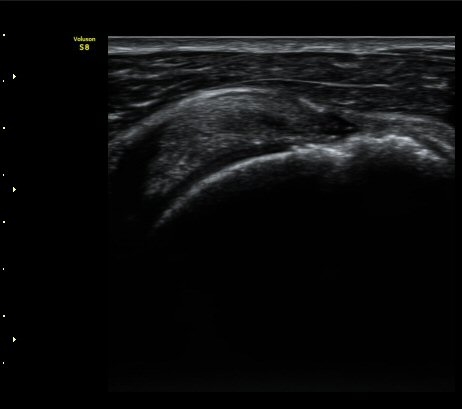

±Ø»ó°Ç ³»Ãø Á¾´Ü¸é°Ë»ç¿¡¼­ ƯÀÌ ¼Ò°ßÀ» º¸ÀÌÁö ¾ÊÀ¸³ª(»çÁø 4)

±Ø»ó°Ç ¿ÜÃø Á¾´Ü¸é°Ë»ç¿¡¼­ ±Ø»ó°Ç ºÎÂøºÎ Àú¿¡ÄÚ °á¼Õ°ú ´ë°áÀýÀÇ ºÒ±ÔÄ¢º¯È­°¡ °üÂûµÊ(»çÁø 5)

±Ø»ó°Ç ±ÙÀ§ºÎ Ⱦ´Ü¸é°Ë»ç¿¡¼­ ±Ø»ê°Ç ¿ÜÃøºÎÀÇ Àú¿¡ÄÚ ºÎÁ¾ÀÌ °üÂûµÇ°í(»çÁø 6)

±Ø»ó°Ç ¸»´ÜºÎ¿Í ºÎÂøºÎ¿¡¼­ ÈûÁÙÀÇ ±¹¼ÒÀû Àú¿¡ÄÚ °á¼ÕÀÌ °üÂûµÈ´Ù(»çÁø 7, 8).